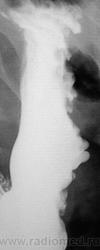

Пол пациента: Женский пол Тип патологии: Другое Область исследования: Пищеварительная система Методы исследования: Rg Один снимок желудка. Может быть мнения будут? https://radiomed.ru/sites/default/files/styles/case_slider_image/public/user/12/2.201201010012.jpg?itok=f3YpbTf6 https://radiomed.ru/sites/default/files/styles/case_slider_image/public/user/12/3.201201010013.jpg?itok=DZdw77nQ https://radiomed.ru/sites/default/files/styles/case_slider_image/public/user/12/4.201311120014.jpg?itok=z9RZUMmQ ID:33225 Ср, 13/11/2013 - 22:10 #1 Дмитрий Волегов Не на сайте Был на сайте: 3 года 6 месяцев назад Зарегистрирован: 22.05.2013 - 00:32 Публикации: 1148 Варикозные вены? С Уважением, Дмитрий. Ср, 13/11/2013 - 22:11 #2 vadim losevichev Не на сайте Был на сайте: 7 лет 2 месяцев назад Зарегистрирован: 27.01.2013 - 09:45 Публикации: 679 Большая кривизна у тела желудка странная. Non progrĕdi est regrĕdi. Ср, 13/11/2013 - 22:11 #3 Катенёв Валенти... Не на сайте Был на сайте: 7 лет 4 недели назад Зарегистрирован: 22.03.2008 - 22:15 Публикации: 54876 Дмитрий Волегов wrote: Варикозные вены? Это стопудово, или дифряд? Ср, 13/11/2013 - 22:25 #4 Дмитрий Волегов Не на сайте Был на сайте: 3 года 6 месяцев назад Зарегистрирован: 22.05.2013 - 00:32 Публикации: 1148 Катенёв Валентин Львович wrote: Дмитрий Волегов wrote: Варикозные вены? Это стопудово, или дифряд? На мой взгляд скиалогия характерная, но опыта мало. В дифряд. С Уважением, Дмитрий. Ср, 13/11/2013 - 22:26 #5 Катенёв Валенти... Не на сайте Был на сайте: 7 лет 4 недели назад Зарегистрирован: 22.03.2008 - 22:15 Публикации: 54876 vadim losevichev wrote: Большая кривизна у тела желудка странная. Да, для нормы странноватая. Ср, 13/11/2013 - 22:32 #6 алкс Не на сайте Был на сайте: 10 лет 4 недели назад Зарегистрирован: 24.10.2012 - 22:55 Публикации: 2915 Лежа бы вниз головой... Ну а так, дефект наполнения по большой кривизне свода. М.б. что угодно, больше за гиперплазию или онко. Ср, 13/11/2013 - 22:37 #7 Катенёв Валенти... Не на сайте Был на сайте: 7 лет 4 недели назад Зарегистрирован: 22.03.2008 - 22:15 Публикации: 54876 алкс wrote: Лежа бы вниз головой... Ну а так, дефект наполнения по большой кривизне свода. М.б. что угодно, больше за гиперплазию или онко. Что угодно быть не может. Протокол писать надо, да и заключение... Ср, 13/11/2013 - 22:37 #8 Катенёв Валенти... Не на сайте Был на сайте: 7 лет 4 недели назад Зарегистрирован: 22.03.2008 - 22:15 Публикации: 54876 алкс wrote: Лежа бы вниз головой... Что даст вниз головой? Это положение Тренделенбурга, или как? Ср, 13/11/2013 - 22:43 #9 алкс Не на сайте Был на сайте: 10 лет 4 недели назад Зарегистрирован: 24.10.2012 - 22:55 Публикации: 2915 Катенёв Валентин Львович wrote: алкс wrote: Лежа бы вниз головой... Что даст вниз головой? Это положение Тренделенбурга, или как? Тугое заполнение свода + можно пасс. рефлюкс, или не там патологию вижу? Просто стол опустить с пациентом ( который стоя стоит) на 10-15градусов без вычурных. Ср, 13/11/2013 - 23:03 #10 stovbav Не на сайте Был на сайте: 2 года 2 месяцев назад Зарегистрирован: 20.12.2009 - 17:28 Публикации: 7066 Почему не локальная форма Менетрие?.... Болезни ног: виды, симптомы, причины, профилактика и лечение Ср, 13/11/2013 - 23:16 #11 алкс Не на сайте Был на сайте: 10 лет 4 недели назад Зарегистрирован: 24.10.2012 - 22:55 Публикации: 2915 stovbav wrote: Почему не локальная форма Менетрие?.... Вполне, не я так написал - "гиперплазия" Ср, 13/11/2013 - 23:20 #12 Катенёв Валенти... Не на сайте Был на сайте: 7 лет 4 недели назад Зарегистрирован: 22.03.2008 - 22:15 Публикации: 54876 stovbav wrote: Почему не локальная форма Менетрие?.... Здравствуйте Виктор Григорьевич! Почему "почему"? "Картинка" то типичная, именно, для болезни Менетрие. Ср, 13/11/2013 - 23:44 #13 stovbav Не на сайте Был на сайте: 2 года 2 месяцев назад Зарегистрирован: 20.12.2009 - 17:28 Публикации: 7066 Катенёв Валентин Львович wrote: stovbav wrote: Почему не локальная форма Менетрие?.... Здравствуйте Виктор Григорьевич! Почему "почему"? "Картинка" то типичная, именно, для болезни Менетрие. Так вопрос то был - риторический))), уважаемый Валентин Львович! Болезни ног: виды, симптомы, причины, профилактика и лечение Чт, 14/11/2013 - 07:53 #14 Андрей Юрьевич Не на сайте Был на сайте: 2 недели 1 день назад Зарегистрирован: 16.11.2008 - 22:16 Публикации: 18098 Менетрие? По одному снимку, без второй порции бария, без шипучки и снимков в горизонтальном положении. Как-то лихо. Андрей Юрьевич Чт, 14/11/2013 - 12:39 #15 stovbav Не на сайте Был на сайте: 2 года 2 месяцев назад Зарегистрирован: 20.12.2009 - 17:28 Публикации: 7066 Андрей Юрьевич wrote: Менетрие? По одному снимку, без второй порции бария, без шипучки и снимков в горизонтальном положении. Как-то лихо. Все это так...но ответ то по ОДНОМУ снимку надо дать...так что - имеем, что имеем: один снимок - и ряд мнений)))) Болезни ног: виды, симптомы, причины, профилактика и лечение Чт, 14/11/2013 - 20:47 #16 И.Бондаренко Не на сайте Был на сайте: 1 день 3 часа назад Зарегистрирован: 13.09.2011 - 22:55 Публикации: 9206 На вашем аппарате тубус (компрессия) есть? Чт, 14/11/2013 - 23:50 #17 Катенёв Валенти... Не на сайте Был на сайте: 7 лет 4 недели назад Зарегистрирован: 22.03.2008 - 22:15 Публикации: 54876 Андрей Юрьевич wrote: Менетрие? По одному снимку, без второй порции бария, без шипучки и снимков в горизонтальном положении. Как-то лихо. Вы правы! Снимок не один, выставлен один для "мозгового штурма". Пациент наблюдается уже в течение пяти лет, консультирован, обследовался и лечился в ОКБ. Чт, 14/11/2013 - 23:52 #18 Катенёв Валенти... Не на сайте Был на сайте: 7 лет 4 недели назад Зарегистрирован: 22.03.2008 - 22:15 Публикации: 54876 И.Бондаренко wrote: На вашем аппарате тубус (компрессия) есть? У нас имеется все. Компрессия не только тубусом и но мягкими "валиками". Пояснения в предыдущем посте. Пт, 15/11/2013 - 00:17 #19 Dima Не на сайте Был на сайте: 7 лет 2 месяцев назад Зарегистрирован: 05.08.2012 - 17:39 Публикации: 2467 Спасибо за интересное наблюдение, Валентин Львович! Если есть возможность покажите пожалуйста все рентгенограммы выполненные в процессе исследования. Терпимость - это когда прощают чужие ошибки; такт - когда не замечают их. (Артур Шницлер)

Лежа бы вниз головой... Ну а так, дефект наполнения по большой кривизне свода. М.б. что угодно, больше за гиперплазию или онко.

"Картинка" то типичная, именно, для болезни Менетрие.

Менетрие? По одному снимку, без второй порции бария, без шипучки и снимков в горизонтальном положении. Как-то лихо.